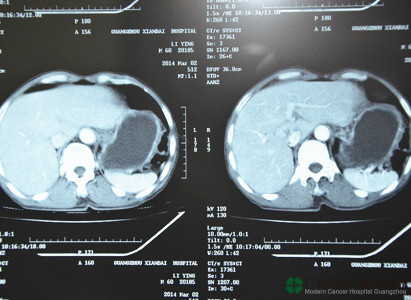

หลังจากที่มาถึงโรงพยาบาลมะเร็งสมัยใหม่กว่างโจว กลุ่มแพทย์จากหลากสาขา (กลุ่ม MDT) ก็ได้ดำเนินการตรวจให้หลี่อิงทันทีเพื่อเตรียมพร้อมในการรักษาภายหลัง ผลการตรวจบอกว่าหลี่อิงเป็นมะเร็งกระเพาะอาหารระยะสุดท้าย กลุ่ม MDT คำนึงถึงว่าสุขภาพเขาค่อนข้างอ่อนแอ จึงเลือกวิธีการที่ค่อนข้างจะครบรอบด้านให้กับเขา และค่อยๆ บรรเทาอาการของเขาทีละขั้นๆ กลุ่ม MDT ใช้วิธีการรักษาเฉพาะจุดผ่านหลอดเลือดก่อน โดยนำยาเข้าไปทางหลอดนำทางจากหลอดเลือดแดงฉีดเข้าไปที่ภายในก้อนมะเร็งที่กระเพาะอาหารโดยตรง อุดช่องทางอาหารของมะเร็ง และยังใช้วิธีการใช้ความเย็น การใช้เซลล์ภูมิคุ้มกันบำบัดร่วมกันเพื่อทำให้เซลล์มะเร็งแข็งตัว และในขณะเดียวกันก็เพิ่มภูมิคุ้มกันร่างกายให้กับหลี่อิงด้วย และเมื่อผ่านการรักษาอย่างต่อเนื่องโดยกลุ่ม MDT อาการของหลี่อิงก็ได้รับการควบคุม ก้อนเนื้อก็มีขนาดเล็กลงด้วย

ก่อนการรักษา

มะเร็งกระเพาะอาหาร

หลังการรักษา